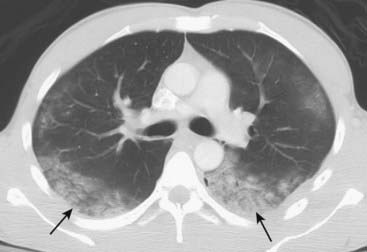

image

Figure 7-10 Aspiration, both lower lobes.

Single, axial CT image of the lungs demonstrates bilateral lower lobe airspace disease in a patient who had aspirated (solid black arrows). Aspiration usually affects the most dependent portions of the lung. In the upright position, the lower lobes are affected. In the recumbent position, the superior segments of the lower lobes and the posterior segments of the upper lobes are most involved. Aspiration of water or neutralized gastric acid will usually clear in 24-48 hours depending on the volume aspirated.